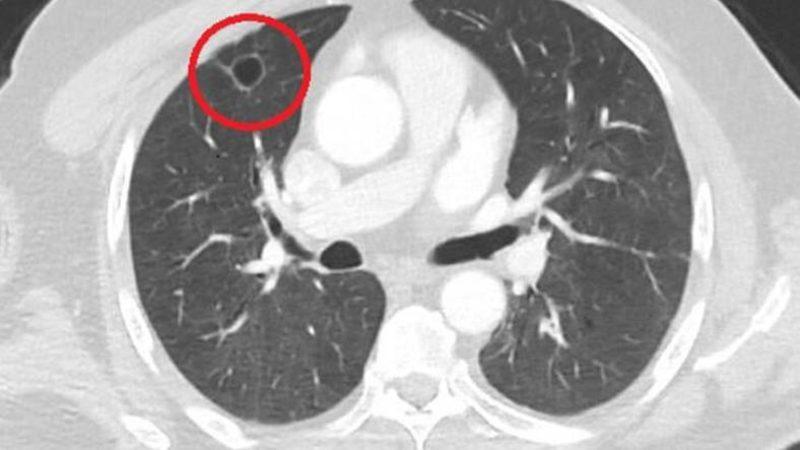

Kozanlı hastanın durumunu "Hastamız, çalıştığı başka bir kentte göğsünden darbe alıyor ve ağrıları geçmeyince bir üniversite hastanesine başvuruyor. Burada hastaya bir akciğer grafisi çekiliyor. Sağ akciğerinde bir kitleye rastlanıyor. Daha sonra hastaya, bir akciğer tomografisi çekiliyor ve göğüs cerrahisi için önemli büyüklükte olan 4 santimetre çapında, akciğer kanserine benzer özellikte radyolojik bulgular olan bir kitle tespit ediliyor. Daha sonra hastaya yapılan ileri tetkiklerde akciğer kanseri teşhisi konuluyor. Hastaya bir cerrahi planlanıyor. Hasta Kahramanmaraşlı olduğu için kendi memleketine gelmeyi tercih ediyor. Bize başvurdu ve göğüs ağrısı şikayeti vardı. Öksürük, nefes darlığı, balgam çıkarma, ateş gibi şikayetleri yoktu. Hastayı biz de değerlendirdik ve ameliyat olmasına karar verdik. Çünkü akciğer kanserine çok benzer radyolojik bulguları vardı. Sağlık Bakanlığımızın kuralları gereği her hastayı ameliyat öncesi PCR testi yapılır. Biz de ameliyat gecesi hastadan PCR testi aldık ve testi pozitif geldi. Ameliyatımızı 14 gün erteledik ve hastamıza koronavirüs tedavisi uygulandı. Hasta 14'üncü gün tekrar bize başvurdu ve yapılan PCR testi negatif çıktı. Yeni bir tomografi çektik ve tümörün tamamen ortadan kalktığını gördük. Şimdi sonuç bilgilerinden başlangıca gittiğimizde, bu bir akciğer kanseri olsaydı, ortadan kalkması mümkün değildi. Başka bir patolojiye bağlı durum olsaydı, yine verdiğimiz tedaviyle ortadan kalkmasını çok beklemeyiz. Antiviral tedavisi verdik ve hastanın radyolojik bulguları neredeyse tamamen normale döndü. Hastaya bunu izah ettik, 'Dünya literatüründe hiç görülmeyen bir radyolojik bulgu' diyerek. Bu gördüğümüz manzara artık hastanın akciğer grafisinde yok, akciğer kanseri değil'' sözleriyle açıklarken varılan sonucun şaşırtıcı olduğunu ifade ediyor.

Hastanın öyküsünü baştan sona incelediğinde koronavirüsün akciğer kanserini taklit ettiği sonucuna ulaştığını ifade eden Kozanlı, bu türden bir vakanın bir ilk olduğunu belirterek durumu "Genel olarak dünya literatürüne baktığımızda koronavirüsün akciğer bulguları, radyolojik bulguları infiltrasyon, buzlu cam dansitesi gibi bilinen bulgular. Ama bizim hastamızda akciğer tümörünü taklit eden bir kitle vardı. Ve biz bunu dünya literatüründe hiç görmemiştik. Bununla ilgili geniş çaplı bir araştırma yaptım. Hem kendi deneyimlerimden hem kendi hastanemizde yatan hastalardan yola çıkarak birçok hastanın radyolojik bulgularına baktık. Dünya literatürlerini karıştırdım, diğer arkadaşlarıma danıştım, benzeri bulguya rastlamadım" sözleriyle açıklıyor.